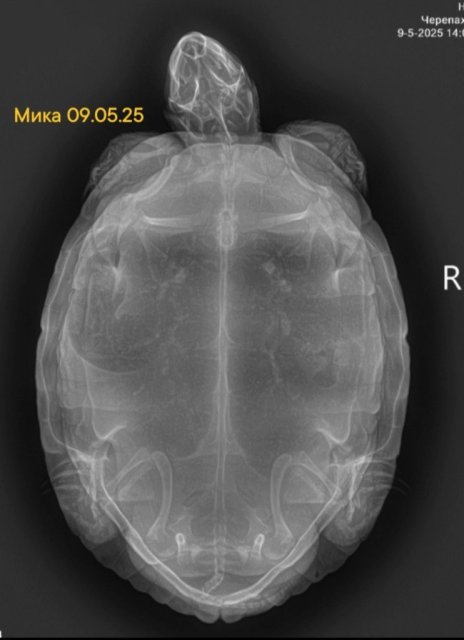

Собрала все её рентгены в кучу. Что можно сказать по последним двум, от 18 июня?

Screenshot_2025-06-23-20-49-43-211_com.vkontakte.android-edit.jpg

Screenshot_2025-06-23-20-44-46-266_com.miui.gallery-edit.jpg

Screenshot_2025-06-23-20-07-36-244_com.miui.gallery-edit.jpg

Screenshot_2025-06-23-20-06-00-118_com.android.chrome-edit.jpg